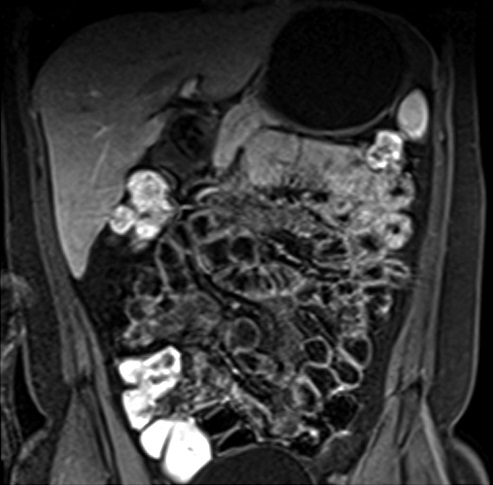

Figura 4

Paciente con enfermedad de Crohn de 10 años de evolución, cursando gestación de 13 semanas. Secuencia eco de gradiente coronal. Asas delgadas de paredes engrosadas en la fosa ilíaca derecha, se idenjpgican los vasos rectos ingurgitados como estructuras lineales perpendiculares a la pared constituyendo el signo del peine (flecha).